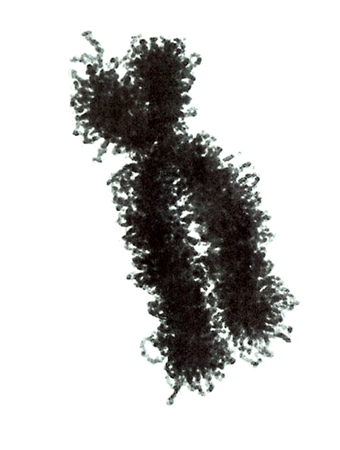

Den berühmten englischen Nobelpreisträgern Watson und Crick gelang vor 50 Jahren die Strukturaufklärung der Chromosomen. Sie konnten zeigen, dass ein Chromosom einem in Schneckenwindungen (Helix) verdrillten Doppelfaden entspricht, der aus vier sich in unterschiedlicher Reihenfolge wiederholenden Nukleotidbasen, der DNA, zusammengesetzt ist. Diese vier Nukeotidbasen sind die vier Buchstaben mit denen unser gesamtes Erbgut buchstabiert, d.h. codiert ist. (» Abb. 2 und » Abb. 3). Jeweils drei Basen (ein Triplet) stehen für eine Aminosäure (Codon).

Der Chromosomenfaden ist so lang, dass er von der Erde bis zum Pluto reichen würde. Das genetische Alphabet der vier Nukleotidbasen stellt ein universelles Prinzip dar und wird zur Codierung des Erbgutes aller Lebewesen, also auch von Mäusen, Flechten, Insekten und Pilze benutzt. Diese Nukleotidbasen haben besondere biochemische Eigenschaften: So treten jeweils zwei in privilegierte Wechselwirkung miteinander. Wenn auf dem einen Chromosomenfaden die Nukleotidbasen A und C buchstabiert werden, finden sich auf dem zweiten komplementären Faden die Basen T und G.